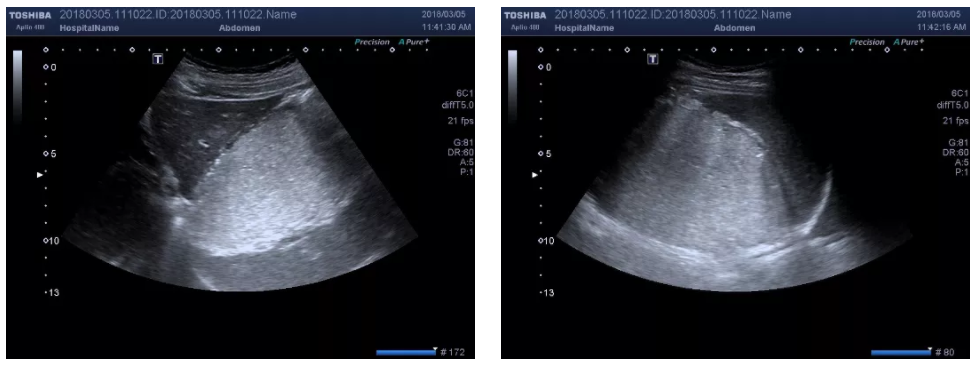

4.胃窦部切面  探头斜置于右上腹(右肋弓和脐之间),声束方向略朝向左上方作斜切扫查,可获得胃窦部长轴切面;在上述探头位置作垂直连续移动扫查,可获得胃窦部短轴切面。

微信截图_20200702170845